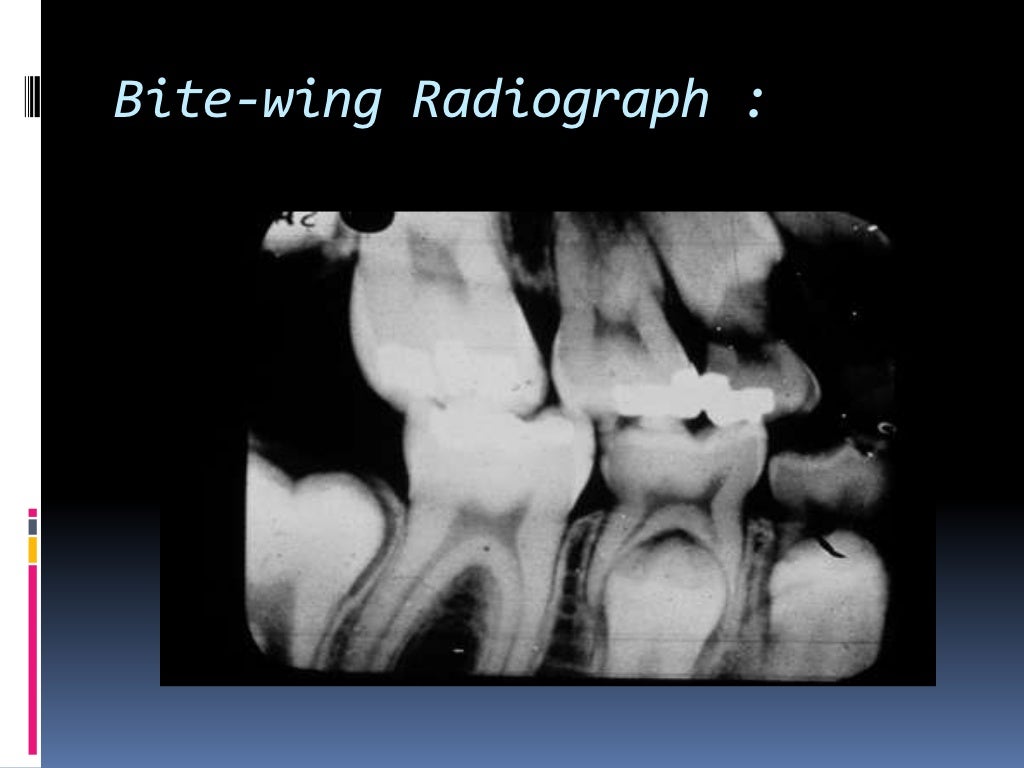

Types of dental radiographs in children Types Of Radiographs Dental Intraoral (inside the mouth) or extraoral (outside the mouth), helping your dentist create a full picture of your. Below, we will explore the most common types of dental radiographs, both intraoral and extraoral, and their applications in dental practice. Find out how they are used, what they show, and how they are safe. These tools enable dentists to. Types Of Radiographs Dental.

Types of dental radiographs in children Types Of Radiographs Dental Find out how they are used, what they show, and how they are safe. Below, we will explore the most common types of dental radiographs, both intraoral and extraoral, and their applications in dental practice. Intraoral (inside the mouth) or extraoral (outside the mouth), helping your dentist create a full picture of your. These tools enable dentists to. Types Of Radiographs Dental.

Types of dental radiographs in children Types Of Radiographs Dental These tools enable dentists to. Intraoral (inside the mouth) or extraoral (outside the mouth), helping your dentist create a full picture of your. Find out how they are used, what they show, and how they are safe. Below, we will explore the most common types of dental radiographs, both intraoral and extraoral, and their applications in dental practice. Types Of Radiographs Dental.